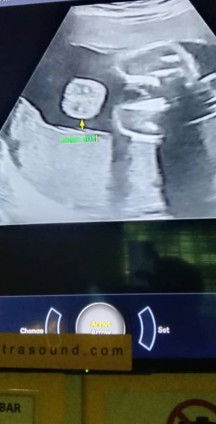

Hi IBU2 baru2 nie saya baru lepas scan anak kedua masa 30week. Boleh bantu tak betul ke apa yang di scan tu jantina boy ye. Sebab sulung dah girl. Mengharapkan yang kedua nie boy.#ingintahu

gambar scan awak nampak ic awak. lebih baik awak edit gelap kan ic awak. ataupon crop sedikit. bahaya. kalau boy mmg jelas nampak gambar pistol dear.